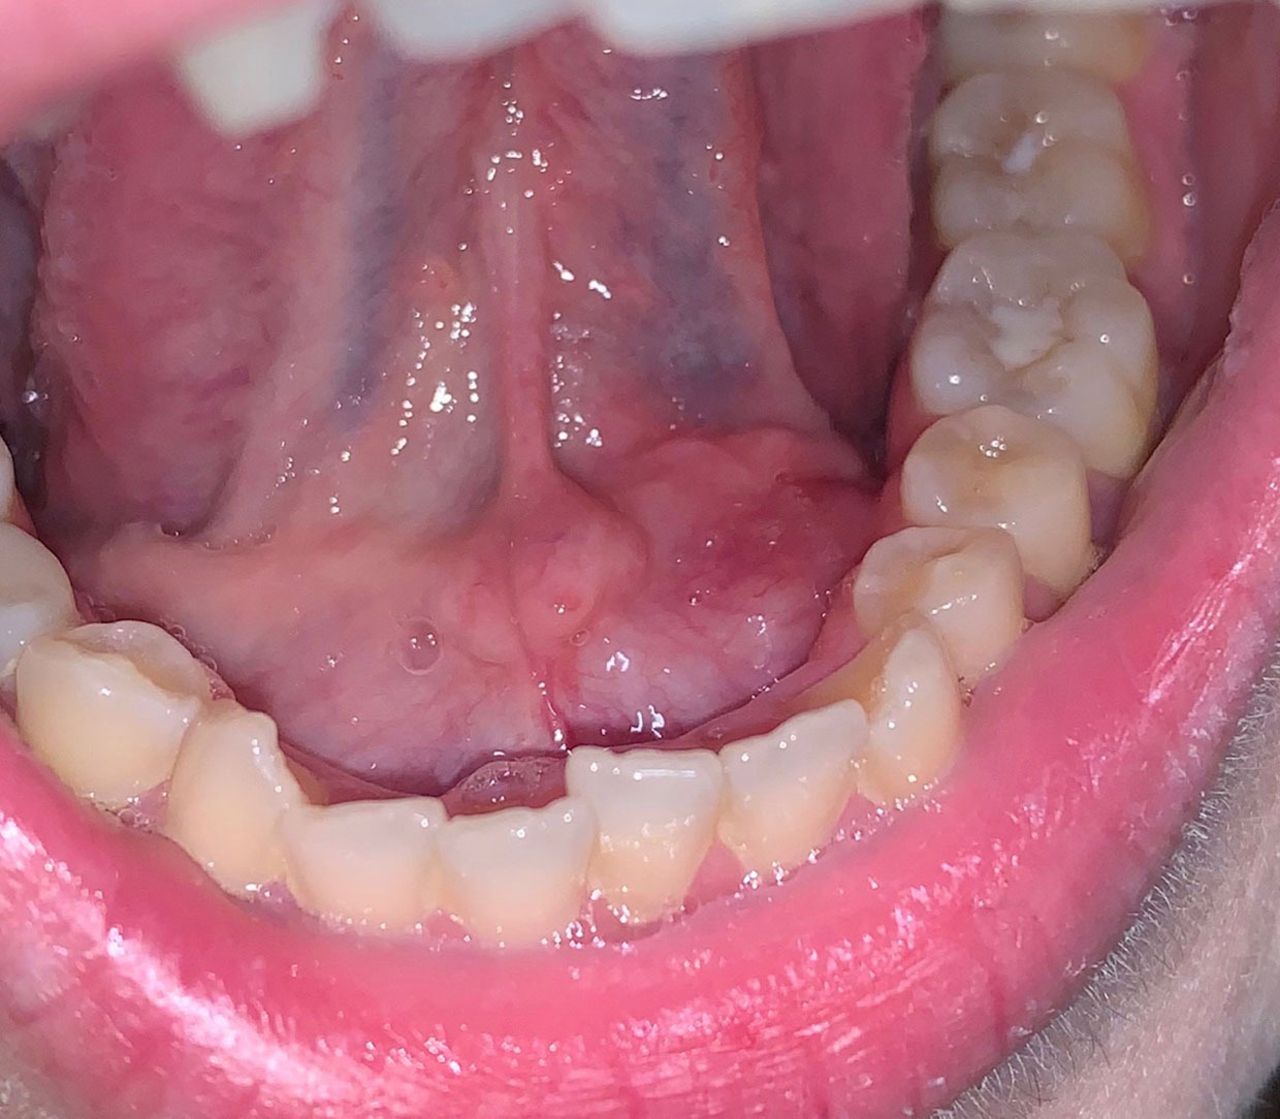

Afecțiuni ale gurii

Afectiunile care pot apărea la nivelul gurii indică o anumită îngustime de spirit, idei și opinii rigide și dificultatea de a accepta și “înghiți” tot ce este nou (gânduri, idei, sentimente, emoții).

Există o situație pe care nu o pot “digera”: cuvinte auzite care m-au deranjat sau m-au rănit sau cuvinte pe care aș fi vrut să le aud și nu s-au spus.

Gesturile sau vorbele celorlalți, care mă rănesc și cărora aș vrea să le răspund, dar nu am avut ocazia, pot provoca afecțiuni ale gurii.

Exemplul tipic este șancrul sau ulcerul bucal (herpesul), care apare de obicei în urma unui stres sau a unui traumatism în timpul sau după o perioadă de stres intens sau după boală.

Acesta indică viziunea mea tristă și nervoasă asupra realității.

Simt o iritare față de ceea ce mi-au făcut sau mi-au spus ceilalți.

Ceva sau cineva mi-a lăsat un gust amar în gură, care mă afectează încă.